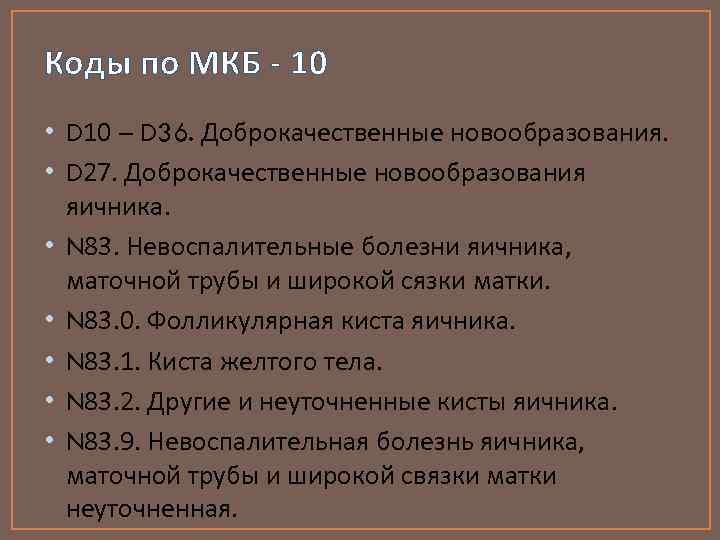

Код мкб 10 атерома головы

Код мкб 10 атерома головы 109 фото